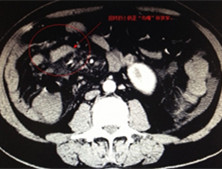

检查项目:

肠道造影、胃肠道CT、腹腔镜